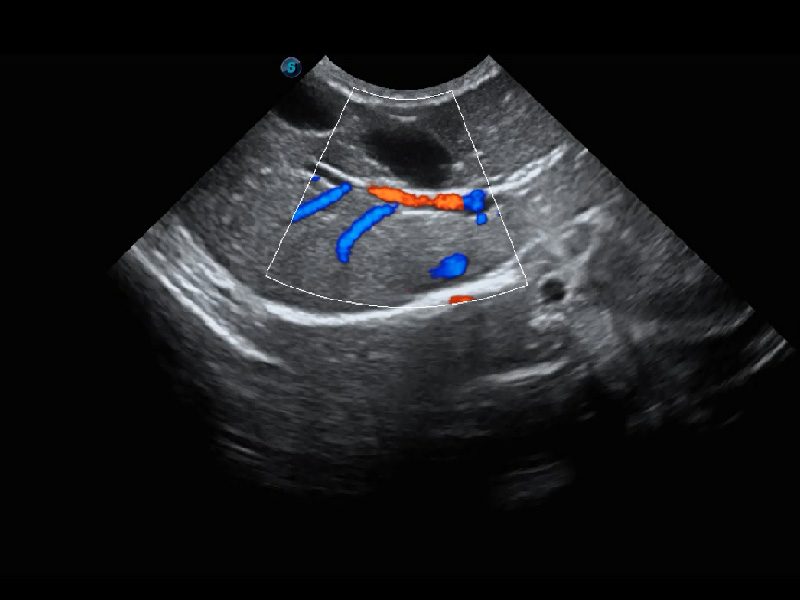

ProPet 60 作为一款高端台式动物超声设备,为动物医生的日常诊断提供了一系列贴合动物临床需求、解决临床实际问题的高级成像功能。凭借全系列高清探头,满足医生对腹部、心脏、生殖、浅表、肌骨等成像的所有需求,切实帮助您提升检查效率,提高诊断信心。

动物是人类最亲密的朋友和最值得信赖的伙伴。美狮贵宾会官网也一直致力于探索动物专用的超声影像解决方案。 全新推出的ProPet系列,是美狮贵宾会官网在动物超声影像智能化、专业化、精准化的一次跨越式革新。动物不能用言语来表述自己的不适,通过超声影像,ProPet系列搭建了动物医生与不同物种沟通的“桥梁”,为动物医生注入了“治愈之力”。